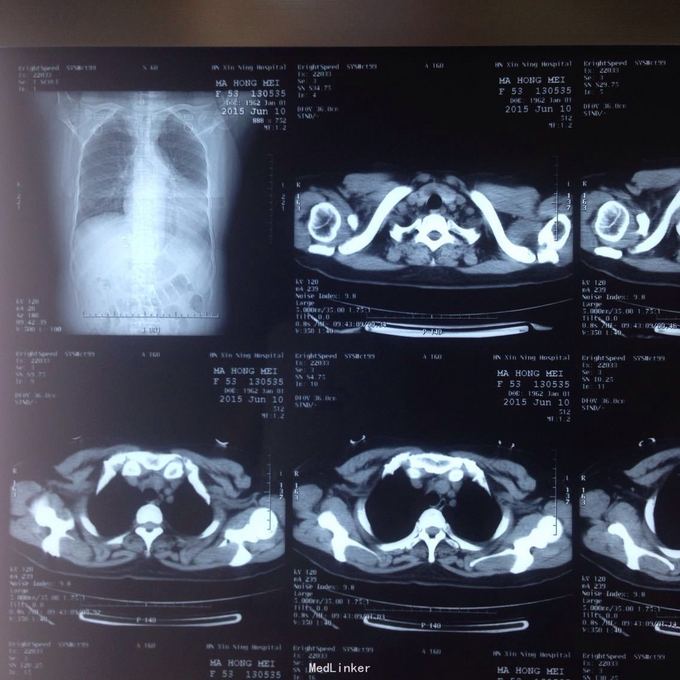

主诉:发现胸腔积液4月余。 现病史:患者4个月前因腰椎间盘突出在当地医院就诊,检查发现双侧少量胸腔积液,量不多,2个月后胸闷气短再次在当地医院复查胸部ct,提示双侧胸腔积液较前增多,左侧明显。

左侧胸腔包裹性积液? 完善胸腔b超提示左侧胸腔包裹性积液,最深处约59mm,内透声较差。予以定位后诊断性穿刺未抽出明显液体,当时考虑液体可能较粘稠或包裹分隔,遂决定予以小切口开胸探查。开胸后见胸腔积液,量约300ml,颜色较清亮,予以抽吸后在探查,见脏层及壁层胸膜无增厚及明显粘连,遂考虑不排除囊肿可能性,继续探查见胸膜顶靠近左纵隔处一囊壁,已破裂,囊壁挛缩成团,予以切除,术后病检为胸腺囊肿。

术后病检为胸腺囊肿。术后讨论:患者多次胸部ct均提示为包裹性积液,因囊肿较大,囊壁较薄,且靠近胸壁,易误诊为包裹性积液,但患者一直无发热病史,且复查ct积液位置靠胸前壁,术前应该考虑到囊肿可能,因患者经济较困难,至本院后未行增强ct,穿刺后考虑穿刺针将囊壁穿破,故开胸后未见完整囊肿,此类看似简单的病例容易由其他医院诊断误导,并且容易误诊。